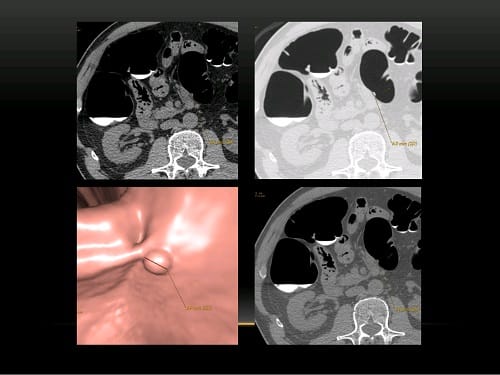

Виртуальная колоноскопия — проводится с двойным контрастированием (пероральный прием контраста и его внутривенное введение при необходимости). Осмотр толстой кишки до самых нижних отделов малого таза, включая прямую кишку, методом компьютерной томографии позволяет определить:

- полипы и иные объемные опухоли стенки кишечника;

- неспецифический язвенный колит;

- дивертикулы;

- окружающие толстую кишку структуры;

- опухоли и метастазы в лимфоузлы толстого кишечника.

Полип кишечника на широком основании, выявленный на виртуальной (КТ) колоноскопии. Исследование выполнено врачом лучевой диагностики КГНЯ Петровой М.А.